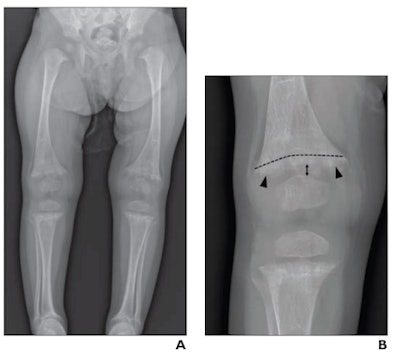

Thus, in this multicenter study, the researchers sought to address the issue by evaluating the diagnostic performance of radiologists in differentiating rickets and CML in children under 2 years old who underwent knee x-rays from January 2017 to December 2018. The children either had rickets (n = 70) or knee CMLs (n = 77) and a diagnosis of child abuse from a child abuse pediatrician.

Images were cropped and zoomed to present similar depictions of the knee, while eight radiologists independently interpreted the x-rays and rated their confidence levels for making diagnoses. Importantly, the radiologists were comprised of both pediatric and nonpediatric specialists with post-training experience ranging from one to 15 years.

According to the findings, the radiologists reached interpretations of rickets and CMLs with substantial to almost perfect agreement. For moderate- or high-confidence interpretations for CML, sensitivity across the eight radiologists was 95.1%, specificity was 97%, and accuracy was 96%.

Other key findings included that children with CML were younger than children with rickets (3.9% vs. 65.7% >1 year old) and that rates of false-positive moderate- or high-confidence interpretations were 0.6% for CML and 1.6% for rickets. Only one child with CML and low vitamin D received an interpretation of combined CML and rickets, the authors found.